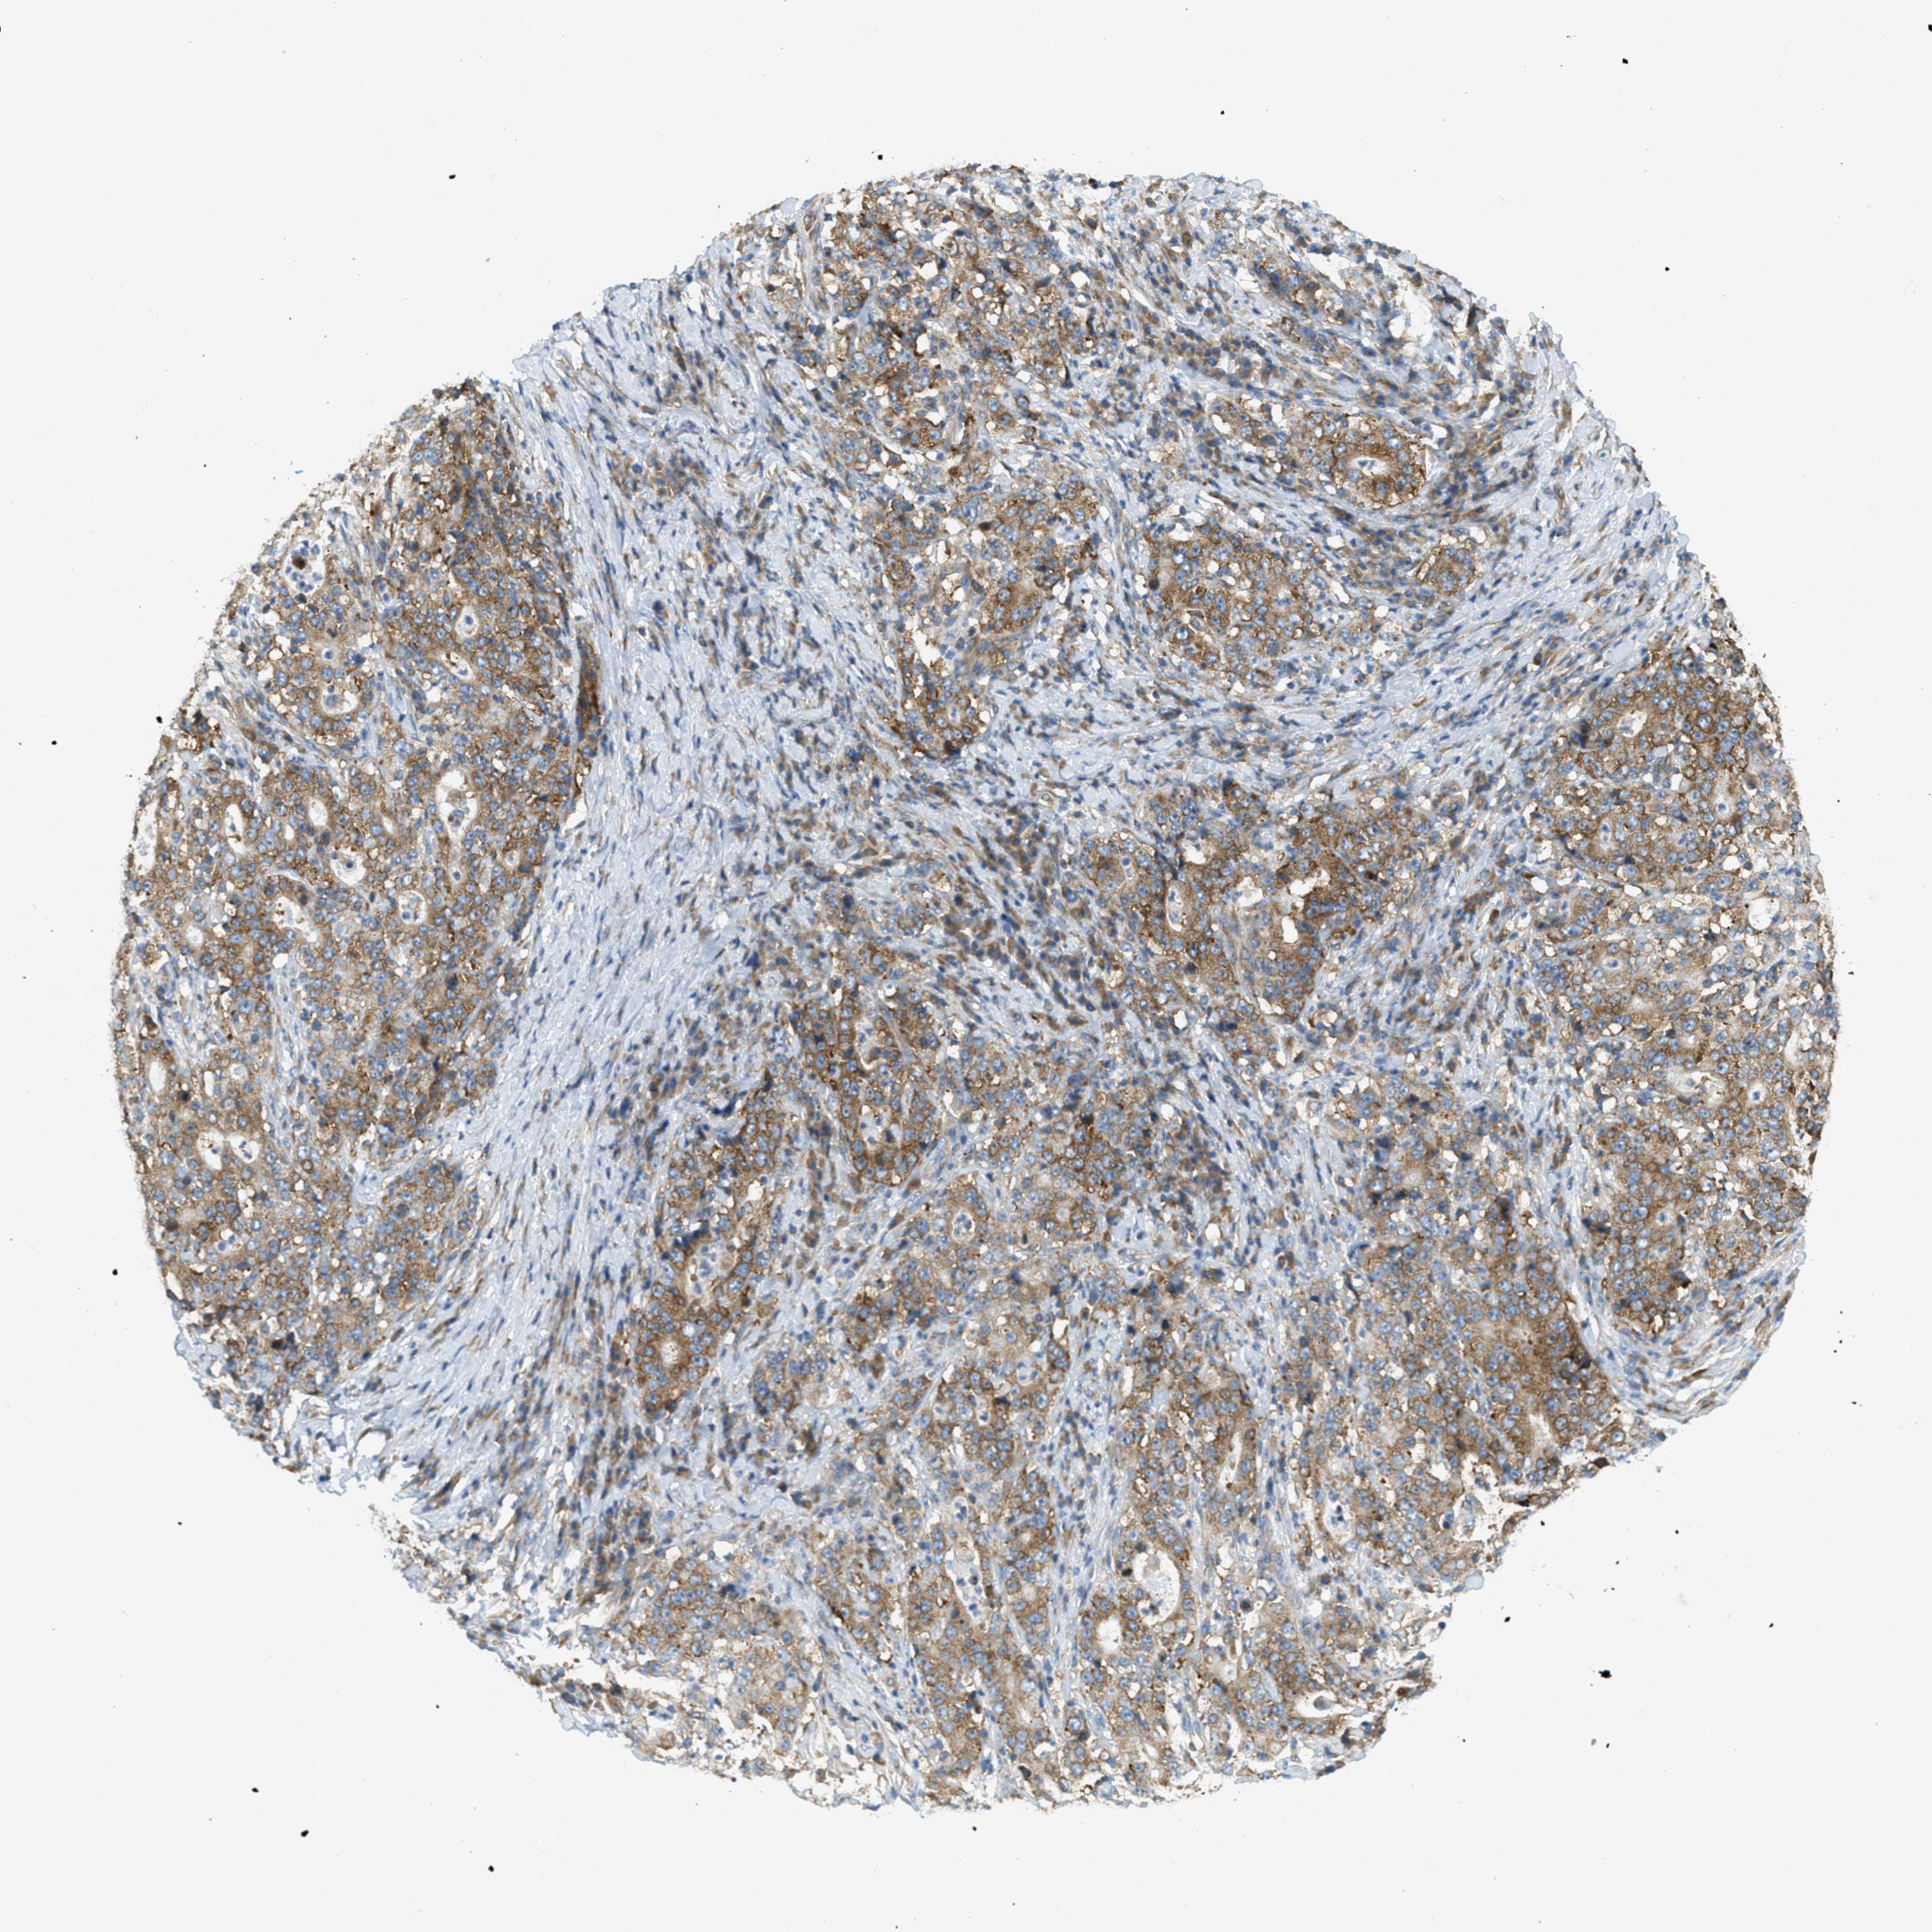

STOMACH CANCER - Protein expressioni

A mouse-over function shows sample information and annotation data. Click on an image to view it in a full screen mode. Samples can be filtered based on level of antibody staining by selecting one or several of the following categories: high, medium, low and not detected. The assay and annotation is described here.

Antibody stainingi

Antibody staining in the annotated cell types in the current human tissue is reported as not detected, low, medium, or high, based on conventional immunohistochemistry profiling in selected tissues. This score is based on the combination of the staining intensity and fraction of stained cells.

Each image is clickable and will lead to virtual microscopy that enables deeper exploration of all samples and also displays staining intensity scores, fraction scores and subcellular localization as well as patient and tissue information for each sample.

Antibody HPA017578

Staining

High

Medium

Low

Not detected

Intensity

Strong

Moderate

Weak

Negative

Quantity

>75%

75%-25%

<25%

None

Location

Nuclear

Cytoplasmic/membranous

Cytoplasmic/membranous,nuclear

Adenocarcinoma, NOS